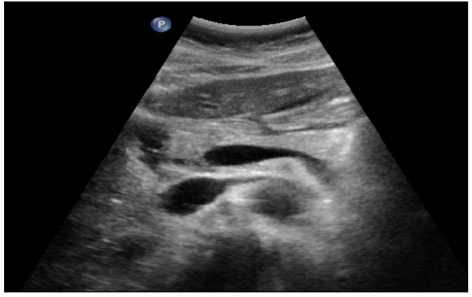

Pancreas

Pancréas